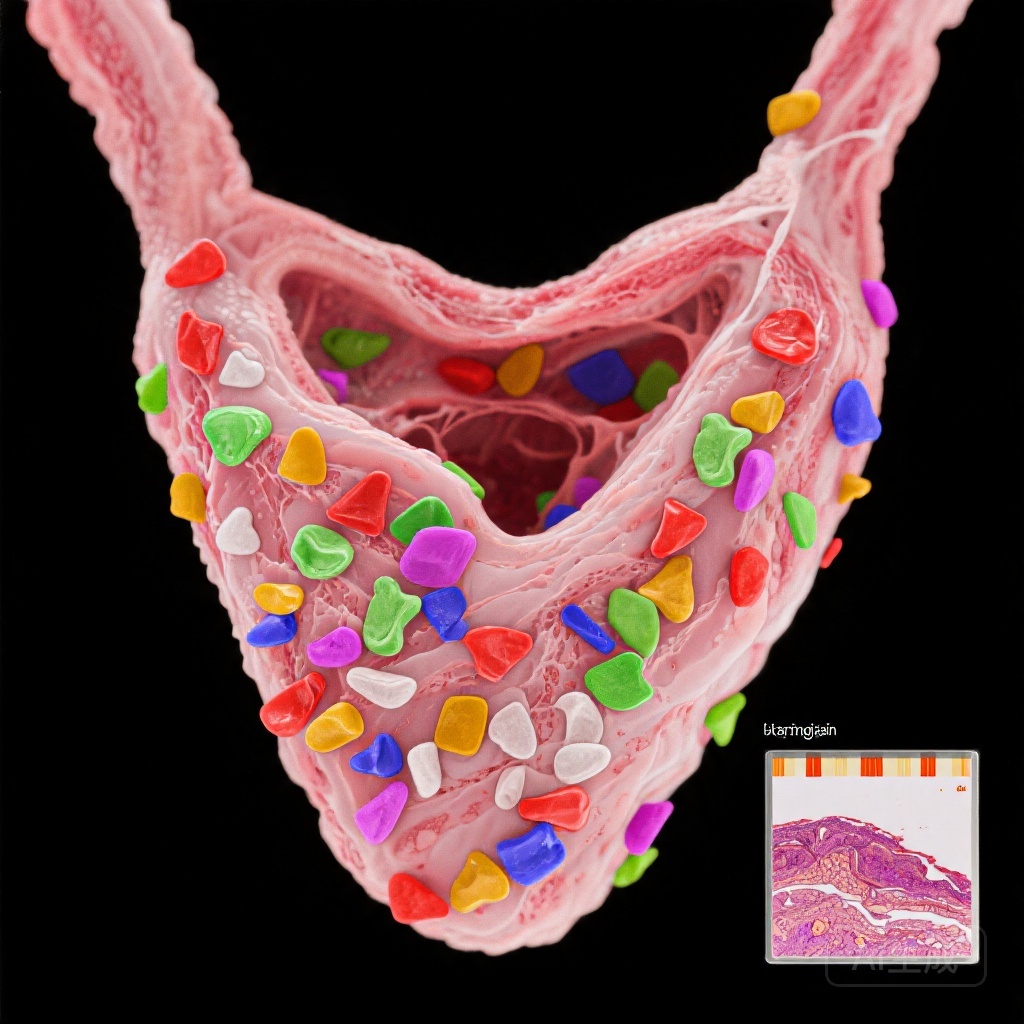

Nghiên cứu này so sánh mô tuyến giáp từ 29 bệnh nhân AIT được xác nhận qua hình ảnh học và 29 đối chứng cùng độ tuổi và giới tính có u tuyến giáp lành tính. MPs được định lượng bằng phương pháp nhiệt phân-gas sắc ký-chromatography-mass spectrometry (Py-GC/MS) và đặc trưng thông qua vi quang phổ Raman và vi kính điện tử quét (SEM).

Tổng nồng độ MPs đáng kể cao hơn ở bệnh nhân AIT (trung vị: 19,9 μg/g so với 1,9 μg/g; p=0,012), với PVC là polyme chiếm ưu thế. Vi quang phổ Raman cho thấy số lượng MPs cao hơn trong mô AIT (172 so với 50,2 đơn vị/g, p=0,037), với kích thước hạt từ 33,9 đến 1467 µm. Đặc điểm hình thái (kích thước, hình dạng, màu sắc) không khác biệt giữa các nhóm.